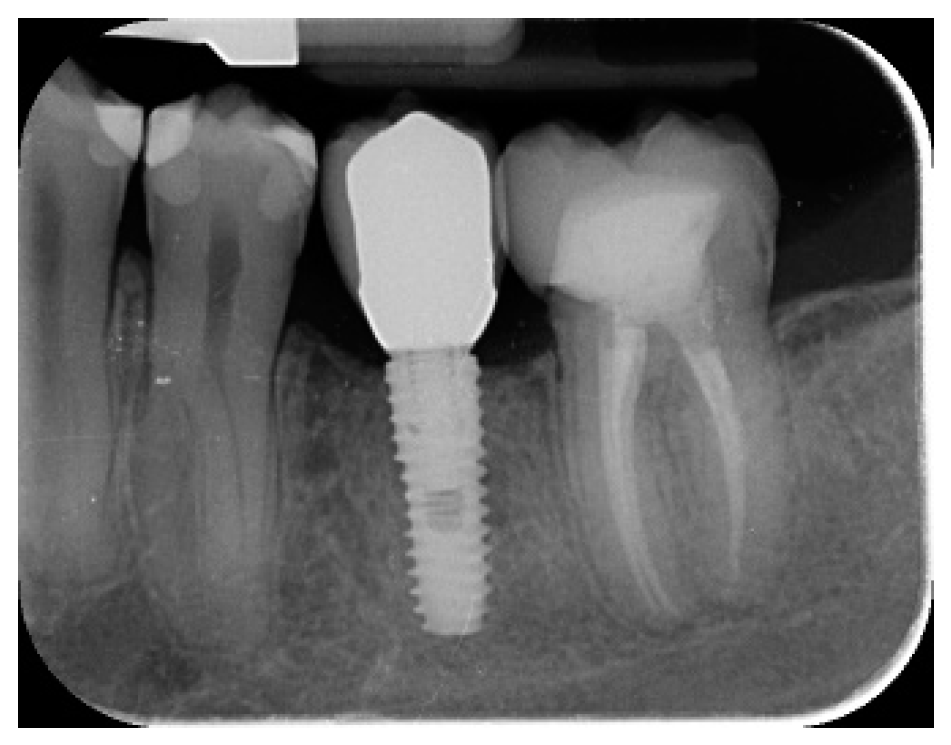

- Marginal bone level changes were assessed by digital periapical radiographs (Digora Optime; Soredex, Tuusula, Finland) using the parallel technique and commercially available film holders. Three time points were evaluated, at implant placement (baseline), immediately after the insertion of the restoration, and one year after loading. The averaged mesial and distal distances from the most coronal margin of the implant and the first bone-to-implant contact was measured to the nearest 0.01 mm and taken as the marginal bone level. The difference in levels between time points was taken as marginal bone loss (MBL).

| Mean marginal bone loss (mm) | 0.13 ± 0.09 (95% CI 0.08–0.19) | 0.28 ± 0.33 (95% CI 0.07–0.50) |